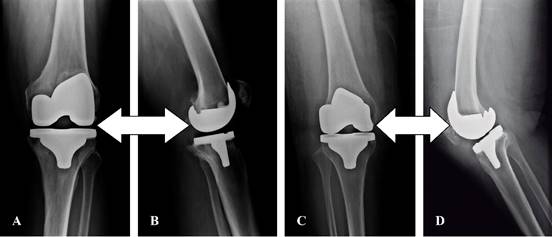

El tipo de prótesis que se utilizó en este estudio fue la posteroestabilizada (Figura 7).